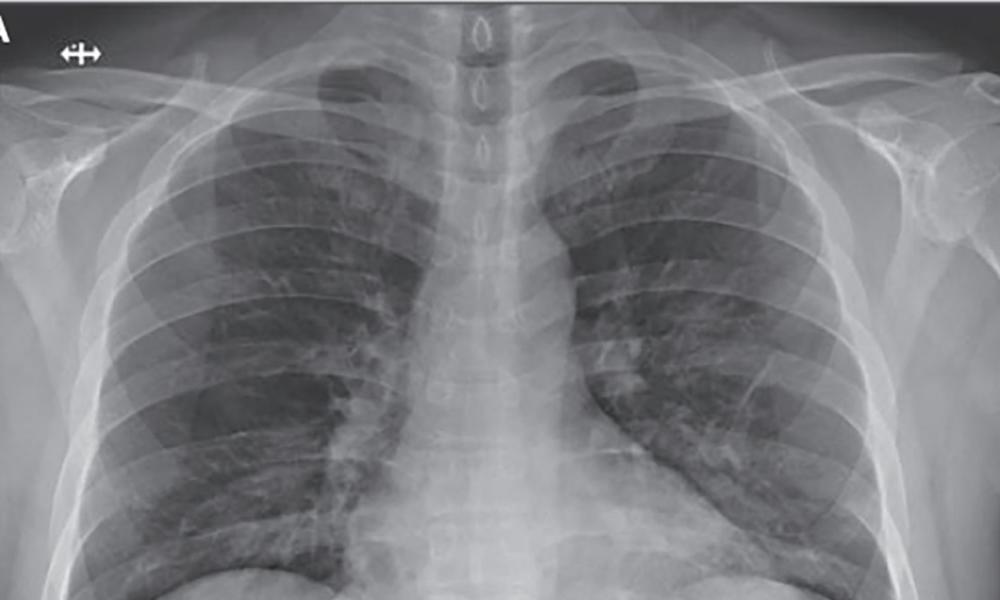

- Δυσκολία στην αναπνοή

Καθώς ο νέος κοροναϊός γενικά επηρεάζει την κατώτερη αναπνευστική οδό, οι περισσότεροι από αυτούς που μολύνονται εμφανίζουν ξηρό βήχα, δύσπνοια, ή πνευμονία, αλλά όχι πονόλαιμο.